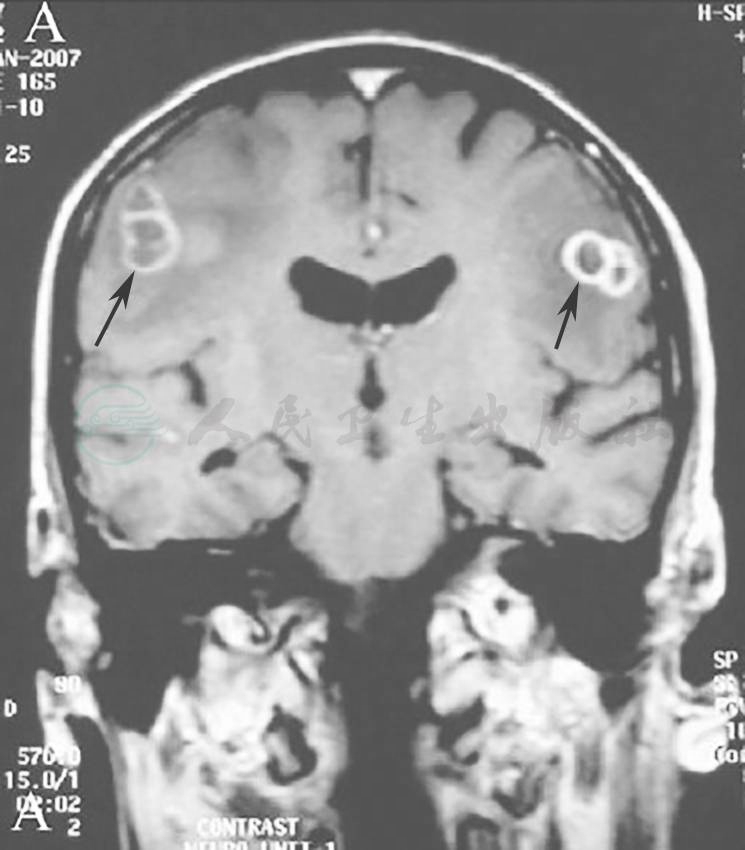

从患者的胸部影像学表现来看,需要警惕血行播散性诺卡菌感染的可能,而这类病变容易合并颅内病变,遂急行头颅MRI,显示颅内多发环形病变(图6),考虑为合并颅内感染。

图6 头颅增强MRI

增强MRI示颅内多发环形增强的占位性病变,周围水肿明显